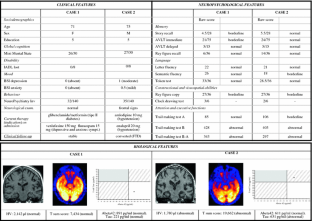

Fig. 1

Fig. 2